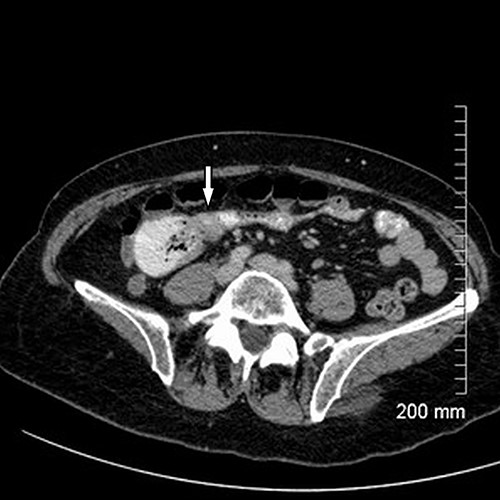

Upon assessment, her abdominal examination revealed tender epigastrium with no palpable mass. A plain abdominal radiograph appeared normal. Subsequently, a computerized tomogram (CT) of her abdomen and pelvis with intravenous contrast was performed, which showed dilated proximal small bowel with a 3-cm stricture and collapsed small bowel distal to the stricture. (Fig. 1). There was lymphadenopathy in the adjacent small bowel mesentery (Fig. 2). A small bowel resection (Proximal Jejunum) was performed through a midline laparotomy. The proximal jejunum was partially obstructed by a 3-cm tumour with multiple lymph nodes visible in the adjacent small bowel mesentery. Resection was done proximally at the duodeno-jejunal (DJ) flexure and distally 15 cm from the tumour in other to perform a satisfactory mesenteric lymphadenectomy (Fig. 3). The third and the fourth parts of the duodenum was partially mobilized and a side-to-side DJ anastomosis was performed.

Axial cut of CT abdomen & pelvis demonstrating strictured segment of small bowel (white arrow).